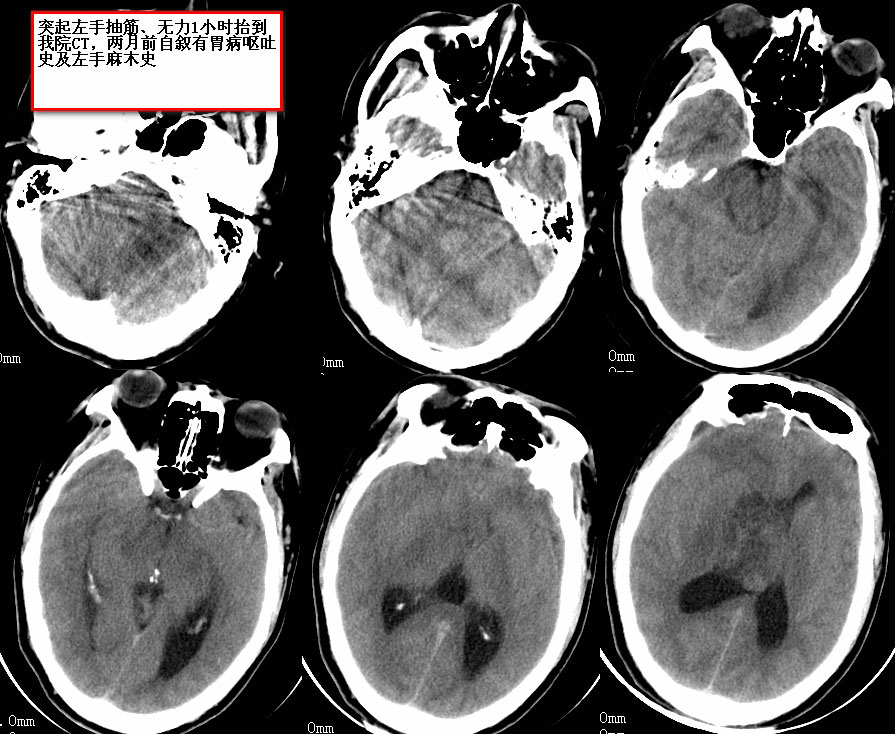

CT26448:头部占位

(结果公布:http://www.radida.com/bbs/forum.php?mod=viewthread&tid=66891) 已去湘雅手术

术后病理结果:胶质瘤3级。

——感谢楼主反馈结果。

恶性胶质瘤可能性大

考虑胼胝体胶质瘤可能性大。